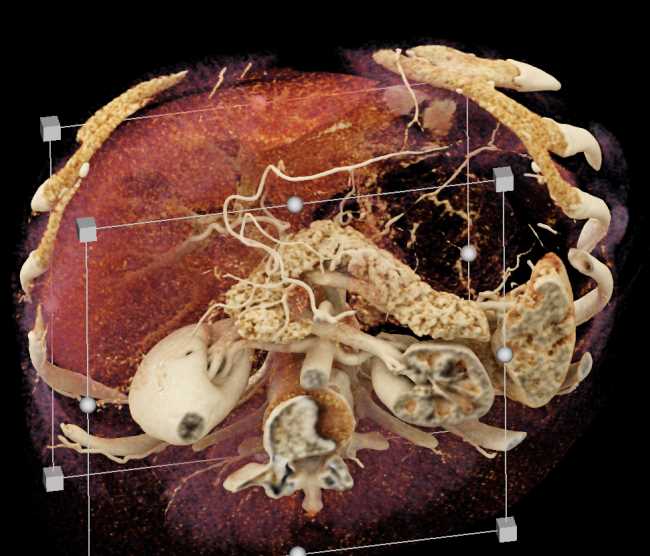

Subtle Neuroendocrine Tumor Body of Pancreas